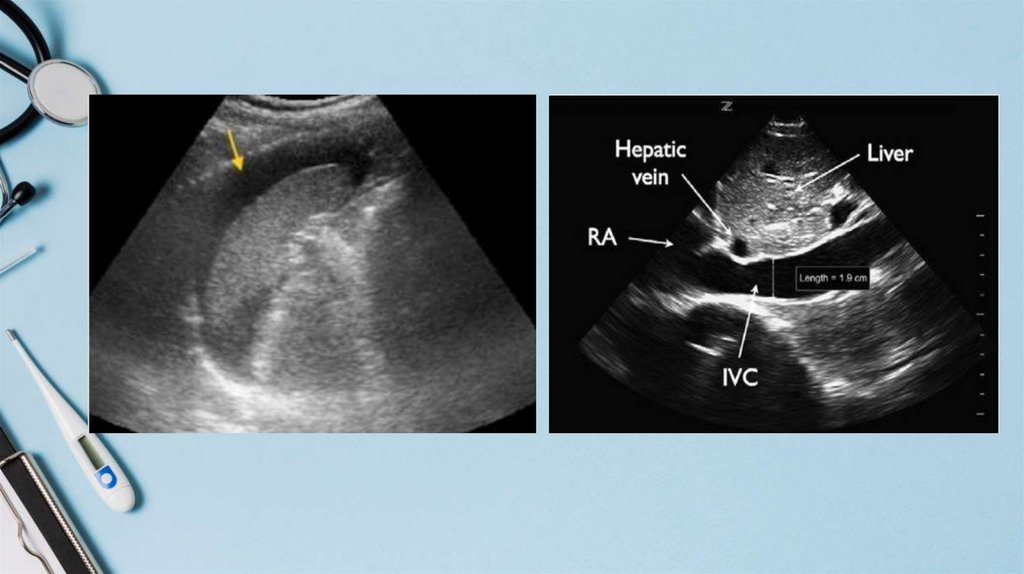

8.

Slide title